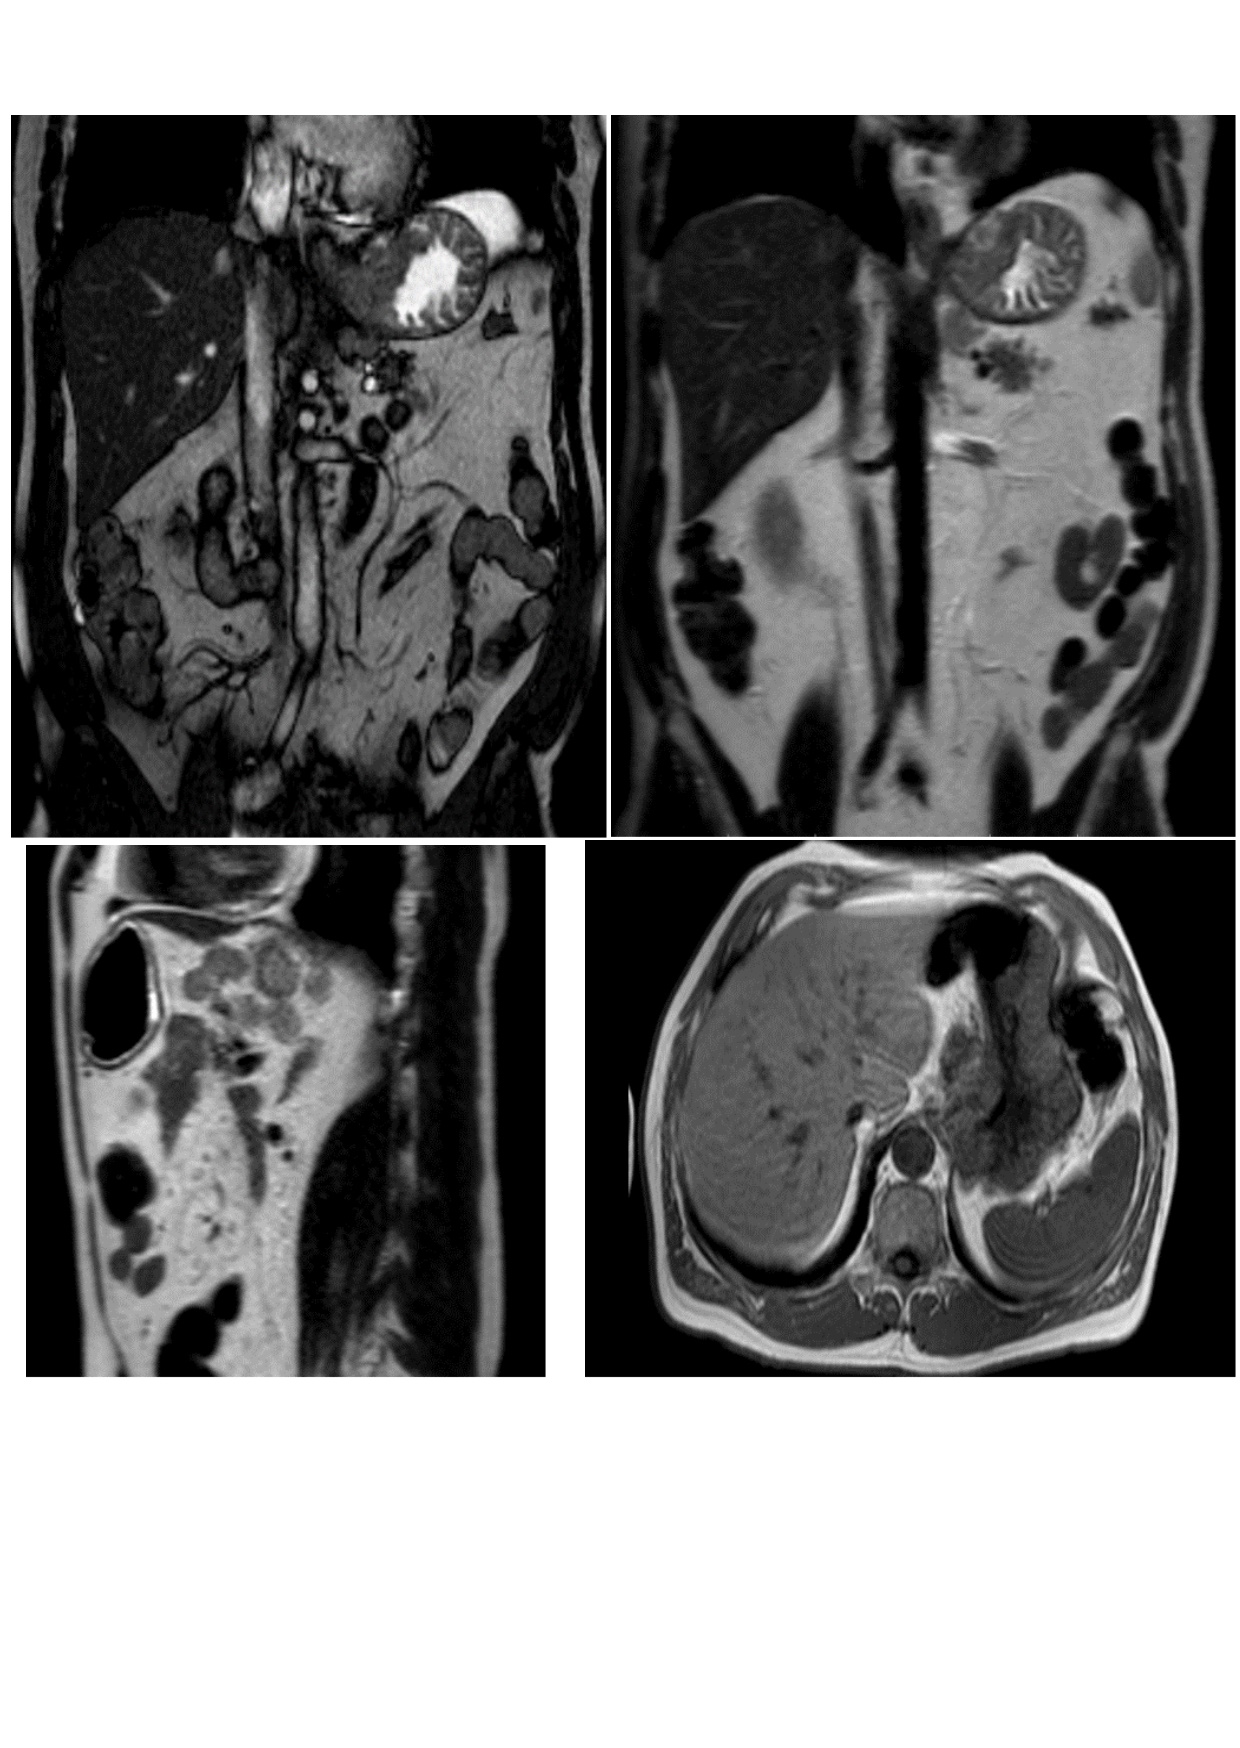

Spread, stage of the oncological process, condition of the surrounding tissues were determined by MRT of the abdominal cavity (Figure 2).

Fig. 2. Results of MRT of the abdominal cavity: Thickening of the gastric wall in the zone of the cardial part (attributable to the neoplastic process with infiltrative growth); near the stomach along the right contour enlarged lymph nodes are determined (right cardiodiaphragmal, of lesser curvature, of the left gastric artery) up to 25x17 mm in size. Conclusion: a picture of voluminous formation in the cardial part of the stomach, regional lymphadenopathy (of metastatic character)